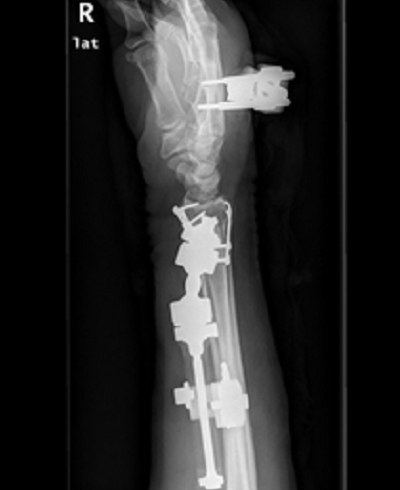

病例二

诊断:陈旧性桡骨远端骨不连,假关节形成,桡腕关节已融合。

治疗:骨不连假关节处植骨融合钢板内固定,尺骨短缩,单边外固定器固定。因桡腕关节已融合,故将单边外固定器反向应用。